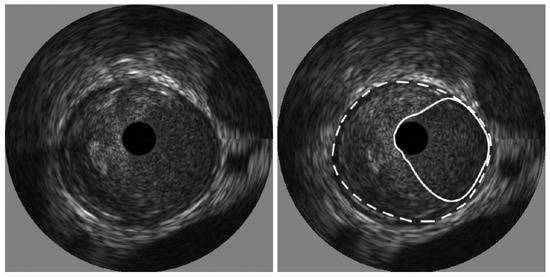

- Destrempes, F.; Cardinal, M.-H.R.; Allard, L.; Tardif, J.-C.; Cloutier, G. Segmentation method of intravascular ultrasound images of human coronary arteries. Comput. Med. Imaging Graph. 2014, 38, 91–103. [Google Scholar] [CrossRef]

- Kermani, A.; Ayatollahi, A. A new nonparametric statistical approach to detect lumen and Media-Adventitia borders in intravascular ultrasound frames. Comput. Biol. Med. 2018, 104, 10–28. [Google Scholar] [PubMed]